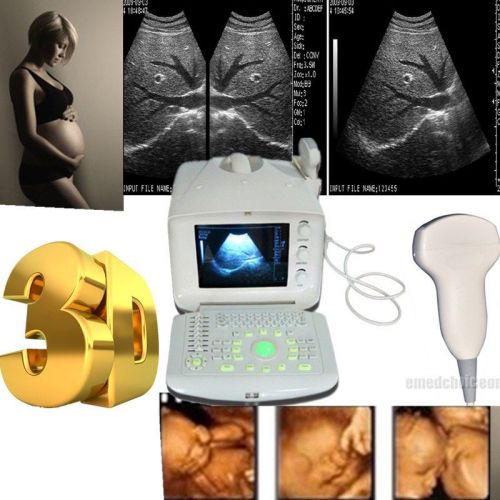

Brand | Ultrasound 9000E2 |

| MPN | Full Digital Ultrasound | ||

| Model | HIGH RESOLUTION | ||

New Full Digital Portable Ultrasound Scanner With Convex+Linear (2 probes) +3D

Digital Ultrasound machine Scanner System Convex linear Probe+3D FDA CE topsell